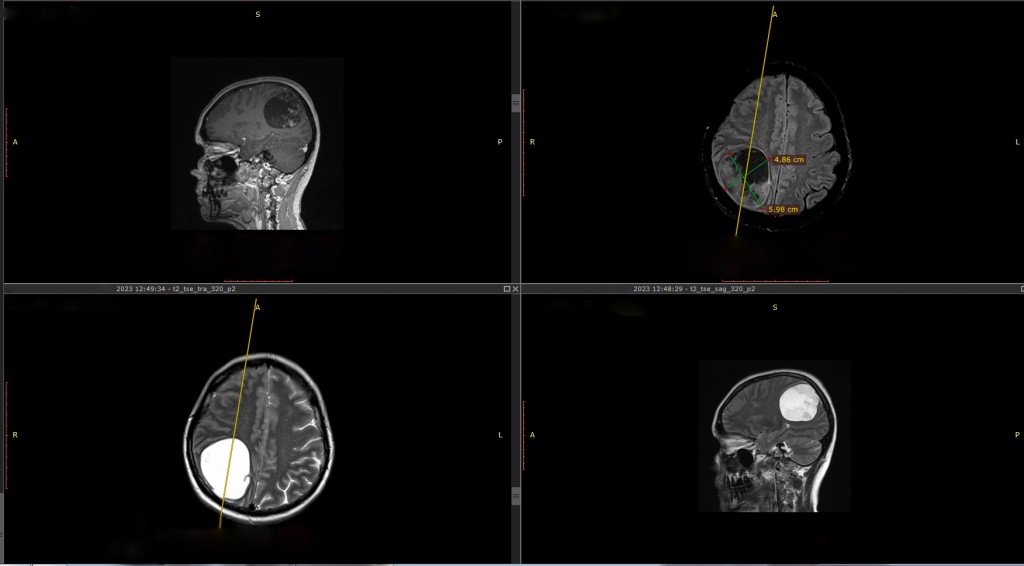

«В пятницу вечером она позвонила мне с жалобами. С учетом трансплантированного сердца и приема иммуносупрессивной терапии, а также онкологического анамнеза, характерна атипичная клиническая картина. Принято решение о ее немедленной госпитализации. В течение часа пациентка была доставлена в Центр Алмазова в сопровождении сестры. Здесь коллеги оперативно выполнили комплексное обследование и были поражены, обнаружив при МРТ головного мозга крупную (6 х 5 х 6 см) опухоль в правом полушарии», — рассказывает врач — кардиолог-трансплантолог клинико-диагностического центра НМИЦ им. В. А. Алмазова Мария Андреевна Симоненко.

На момент поступления у пациентки в неврологическом статусе были выявлены гипертензионный синдром, левосторонняя гемианопсия, легкая статическая атаксия. Консилиум совместно с заведующим отделением нейрохирургии № 5, к.м.н. П. В. Красношлыком и руководителем лаборатории интегративных нейрохирургических технологий, д.м.н. Д. А. Гуляевым, принял решение о проведении хирургического лечения новообразования головного мозга в ускоренные сроки.

8 ноября 2023 года пациентке было выполнено микрохирургическое удаление опухоли правой теменной доли с использованием нейрофизиологического мониторинга. Оперировал врач-нейрохирург профессор Дмитрий Александрович Гуляев.

На следующие сутки после операции больная была переведена из отделения реанимации в палату. Гистологическое исследование подтвердило предполагаемый диагноз: метастаз миксофибросаркомы сердца. Простыми словами, злокачественная опухоль, удаленная вместе с сердцем все-таки, дала метастаз в головной мозг. Стоит отметить, что первичные опухоли сердца встречаются очень редко. При этом миксофибросаркомы составляют менее 1 % от всех опухолей сердца. А вот чтобы рак еще и распространился в мозг – таких случаев в мире единицы.